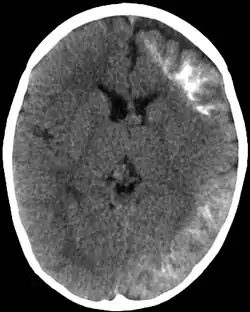

| CT scan of Sturge-Weber syndrome | |

Sturge–Weber is an embryonal developmental anomaly resulting from errors in mesodermal and ectodermal development. Unlike other neurocutaneous disorders (phakomatoses), Sturge–Weber occurs sporadically (i.e., does not have a hereditary cause). It is caused by a mosaic, somatic activating mutation occurring in the GNAQ gene.[2] Imaging findings may include tram track calcifications on CT, pial angiomatosis, and hemicerebral atrophy.[3]

CT and MRI are most often used to identify intracranial abnormalities. When a child is born with a facial cutaneous vascular malformation covering a portion of the upper or the lower eyelids, imaging should be performed to screen for intracranial leptomeningeal angiomatosis. The haemangioma present on the surface of the brain is in the vast majority of cases on the same side as the birth mark and gradually results in calcification of the underlying brain and atrophy of the affected region.[5]